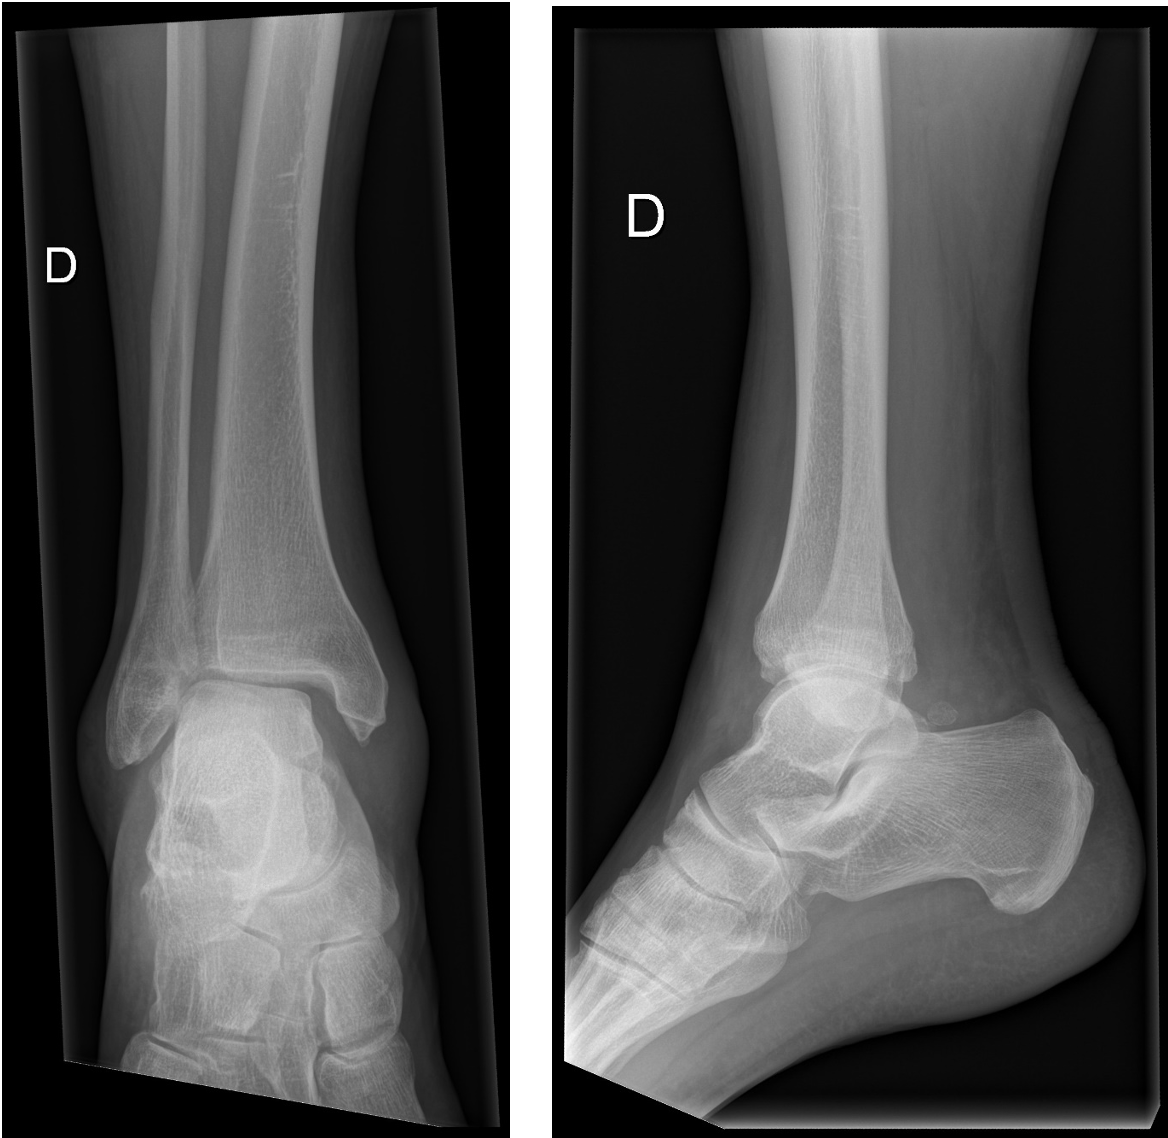

Tu effectues des radiographies face et profil de la cheville droite :

Après avoir vu ces radiographies, comment envisages-tu la suite de la prise en charge ?